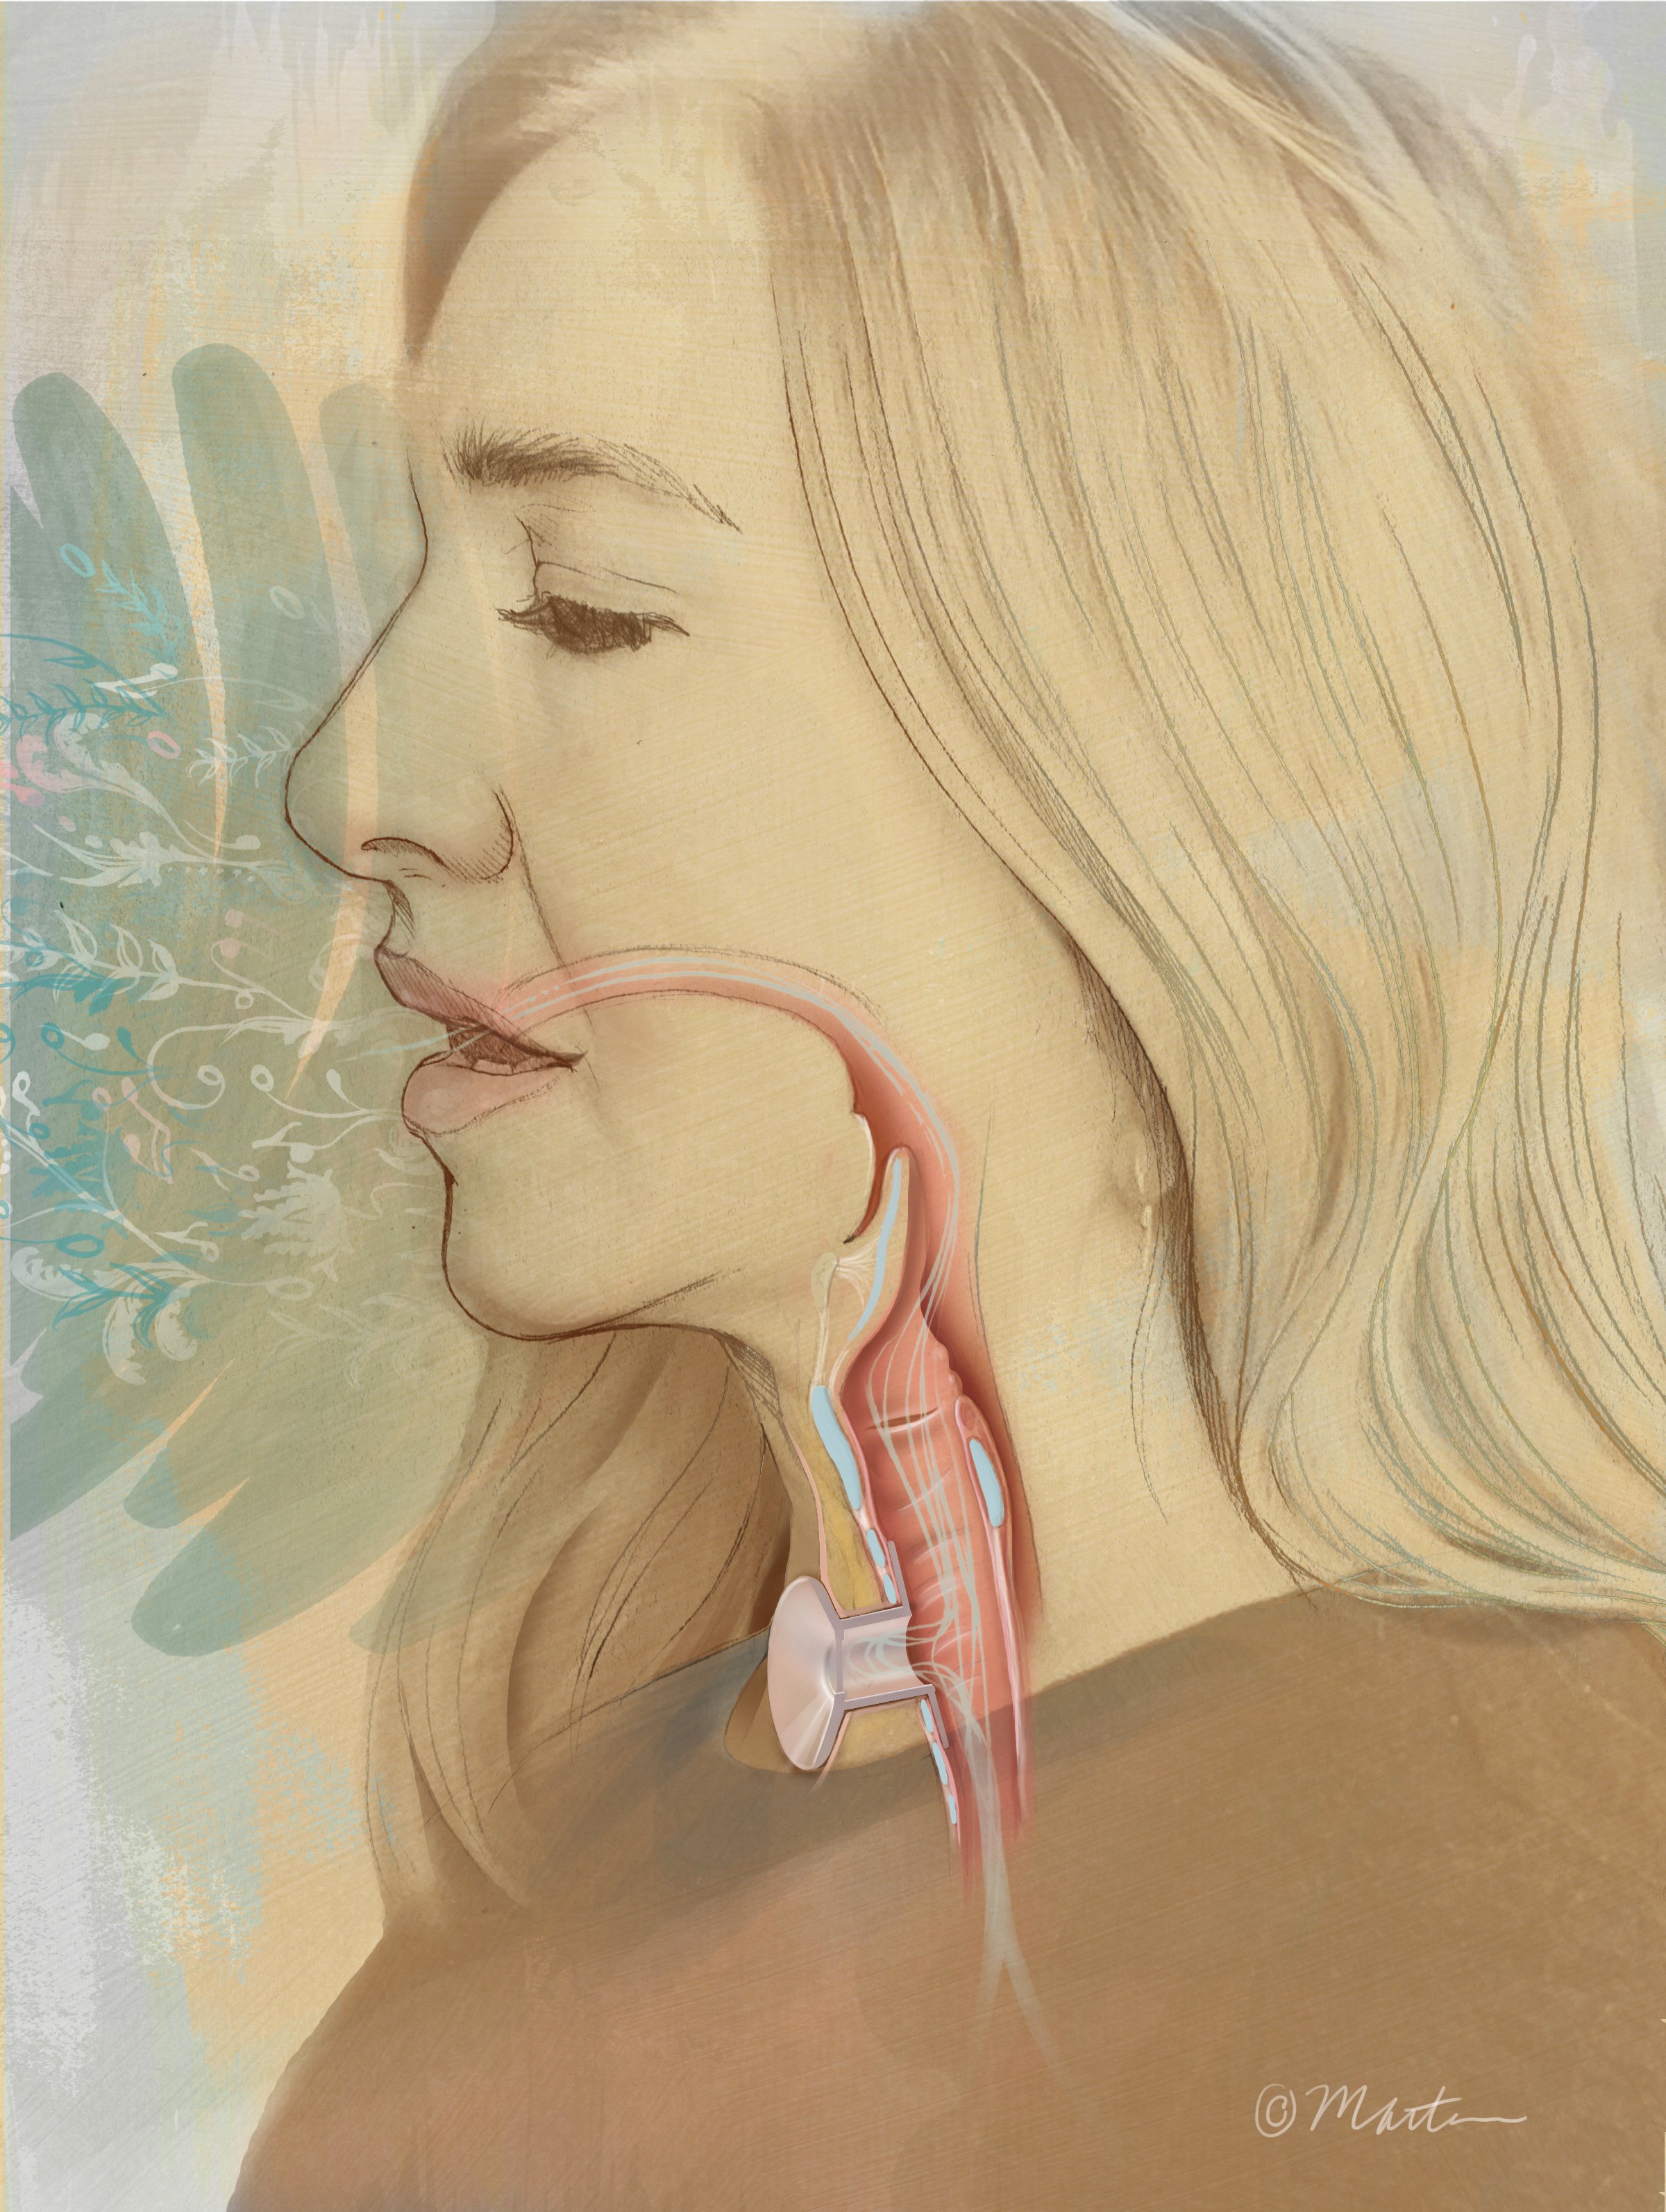

Pessary

Speech After Tracheostomy

Tracheal Transplant